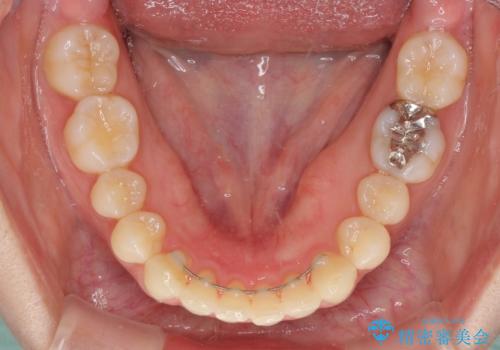

インビザラインによるディープバイトの改善

- 口元の前突感と深い咬み合わせ(ディープバイト)を気にして来院された患者様です。

インビザラインによる上下歯列の遠心移動(後方移動)と、それに伴う近心傾斜(前方傾斜)の改善により、口元の突出感とディープバイトを改善することとしました。

前歯のデコボコを最も気にしていましたが、咬み合わせが深く歯ぎしりが自由にできない点を指摘すると、常に食いしばってしまうことも悩みであることが分かりました。

咬合状態が大きく変化したため、治療後半では咬み合わせの位置が定まらなくなりました。上下の前歯に後戻り防止用のワイヤーを装着し、奥歯の咬合をフリーにしたことで1ヶ月ほどで咬み合わせが定まりました。